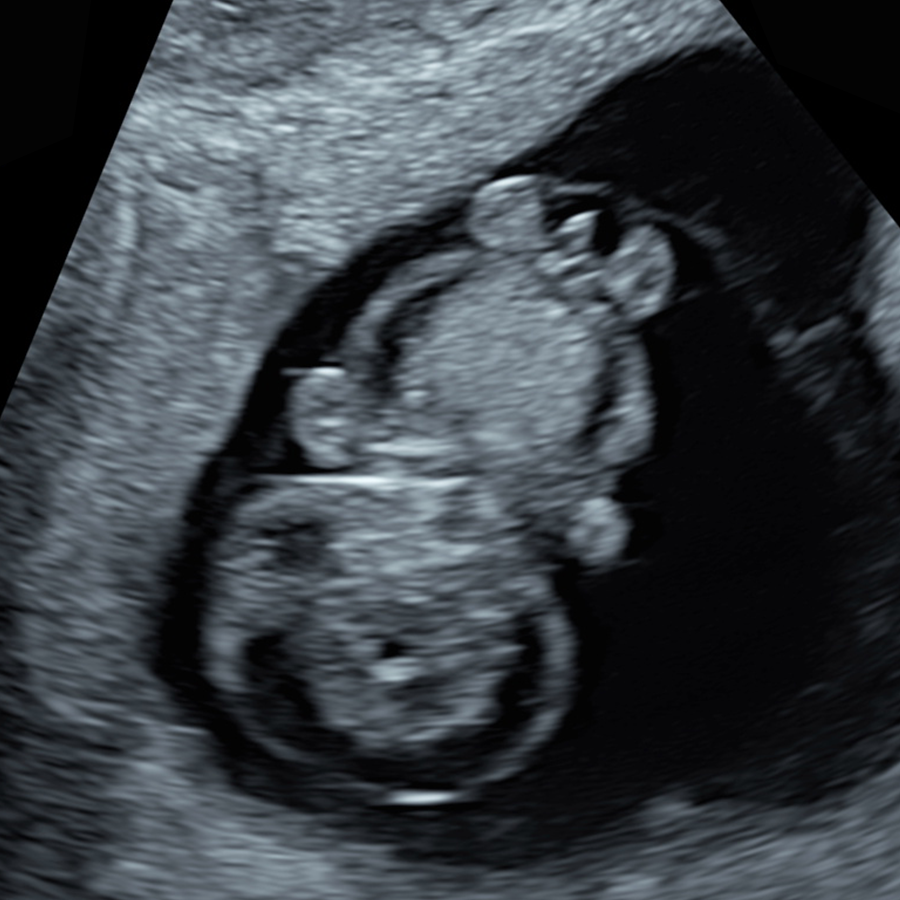

There are three different periods when nuchal thickness can be measured

At 10 weeks, NT can be measured accurately and may be a more sensitive early sign of possible problems, allowing prompt reassurance or testing.

This is the traditional time for NT assessment as part of the Combined Screening Test (CST). In the UK and many other countries, most babies have their NT measured during this stage of pregnancy.

After 14 weeks, the fluid behind the baby’s neck usually disappears, making the NT measurement unreliable. Instead, a different marker called the nuchal fold (NF) can be measured at this stage.